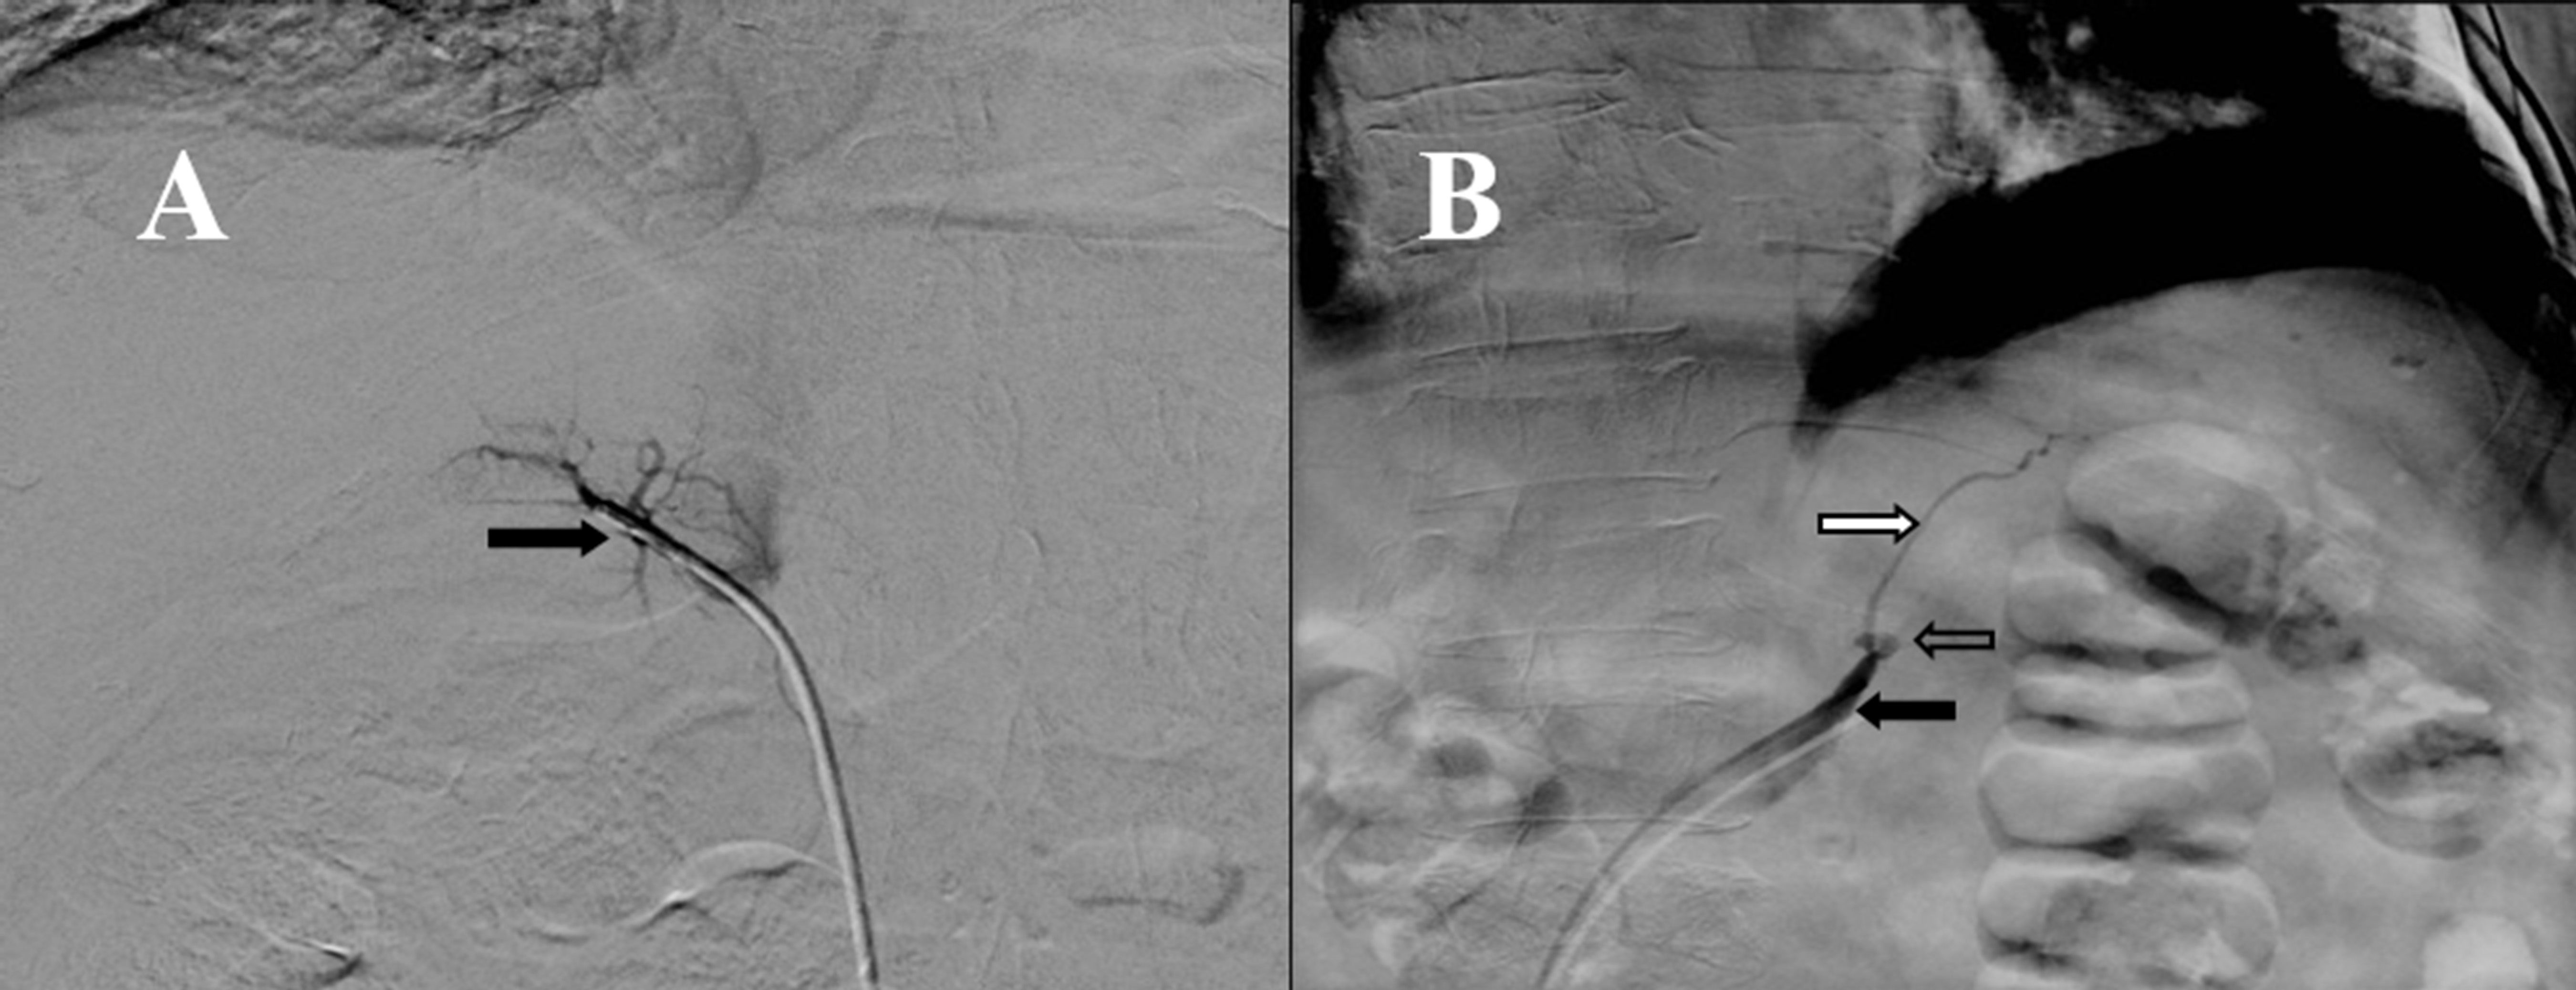

Figura 1.

Tomografía de abdomen. Nódulo en la glándula adrenal derecha de 14x9 mm y en la glándula adrenal izquierda de 23x18 mm

Paciente de 76 años con antecedente de hipertensión arterial controlada con 2 antihipertensivos (losartan y amlodipino) quien consultó por un cuadro clínico de pérdida de peso objetiva de 4 kg en dos meses, edema que progresó hasta la anasarca y dolor dorso-lumbar. Dentro de los estudios solicitados, se documenta en una tomografía de abdomen, un nódulo en la glándula adrenal derecha de 14x9 mm y en la glándula adrenal izquierda de 23x18 mm (Fig. 1), adicionalmente como causa del dolor lumbar se evidencian múltiples fracturas vertebrales desde la quinta vértebra cervical, en múltiples vértebras dorsales y en todas las vértebras lumbares. Como parte del estudio de los adenomas adrenales la paciente tenía un valor anormal de cortisol después de un test de supresión con bajas dosis de dexametasona (13.3 µg/dL, valor normal: <1.8 µg/dL), un valor de cortisol libre urinario normal y un nivel de potasio bajo (no se encontraba en tratamiento con diuréticos). Su examen físico aparte de los edemas era completamente normal sin signos clínicos que sugirieran hipercortisolismo. En la Tabla 1 se muestran los resultados de los principales paraclínicos de la paciente.